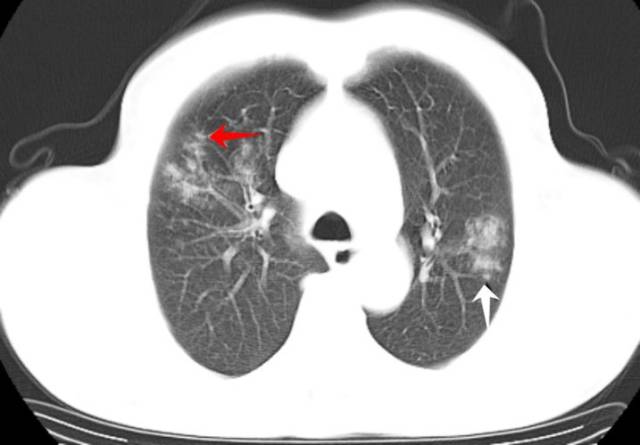

金黄色葡萄球菌肺炎,大咖教你看ct片!

肺炎的CT图片

肺炎ct图片图解